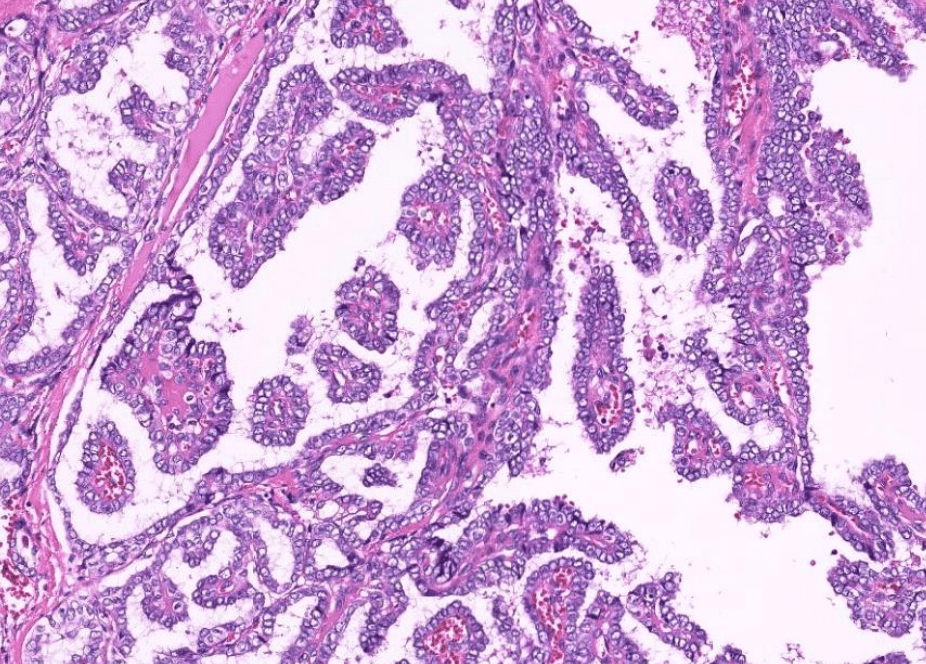

lung adenocarcinoma